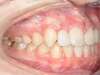

Cas 3 : Description

Encombrement aux deux arcades.Traitement par gouttières.

Avant

Après